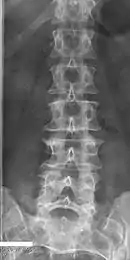

Butterfly vertebrae

Butterfly vertebrae have a sagittal cleft through the body of the vertebrae and a funnel shape at the ends. This gives the appearance of a butterfly on an x-ray. It is caused by persistence of the notochord (which usually only remains as the center of the intervertebral disc) during vertebrae formation. There are usually no symptoms. There are also coronal clefts mainly in skeletal dysplasias such as chondrodysplasia punctata. In dogs, butterfly vertebrae occur most often in Bulldogs, Pugs, and Boston Terriers.[9]